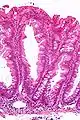

Histopathologie

La partie profonde des glandes est souvent élargie, a tendance à se diviser en deux ou trois branches et à s’horizontaliser, c'est-à-dire à se disposer parallèlement à la musculaire muqueuse et non pas perpendiculairement à elle, comme dans les polypes hyperplasiques conventionnels et les adénomes festonnés traditionnels.